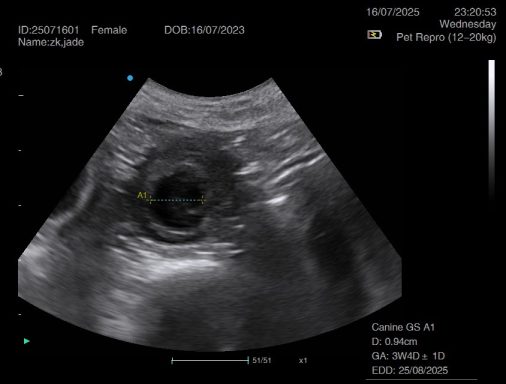

Ultrasound pregnancy scanning is a safe, non-invasive way to confirm pregnancy in dogs and cats, offering breeders and pet owners peace of mind and vital information to support responsible care. It allows us to detect gestational sacs, assess foetal development, and estimate litter size—all while ensuring the wellbeing of the animal.

Pregnancy can sometimes be detected as early as Day 18 post-mating, but scanning at this stage is not routinely recommended. Embryos are still developing and may not be clearly visible, and there is a natural risk of embryo resorption, which can lead to misleading or inconclusive results.

For the most accurate and reliable scan, we advise booking between Day 25 and Day 32, when pregnancy is more easily confirmed and foetal structures are clearer. If an early scan is performed and no pregnancy is detected, we offer a FREE complimentary re-scan after 7 days at the clinic to ensure clarity and support informed decision-making.

Our approach balances early insight with ethical care—always prioritizing the comfort of the animal and the accuracy of the results.

Gallery